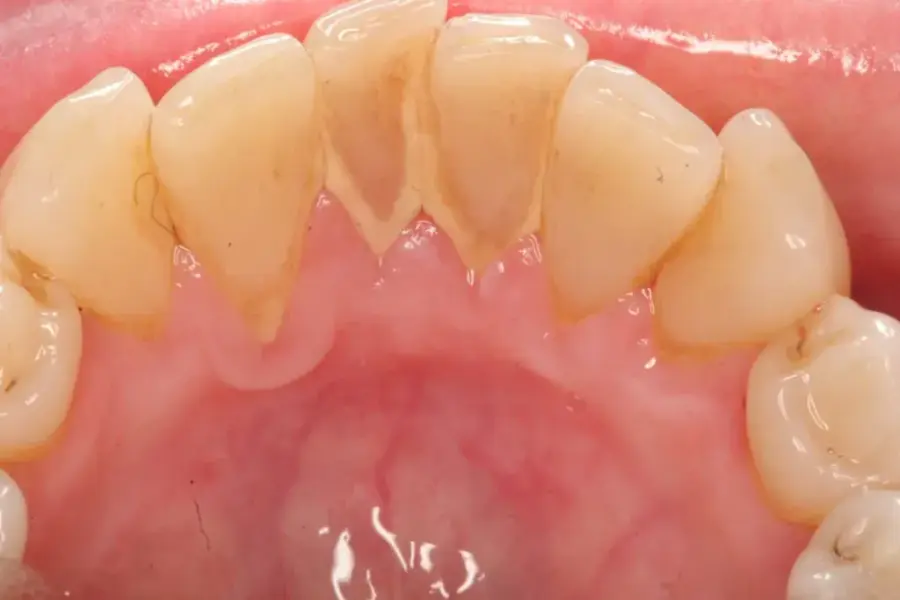

Màng sinh học

Tìm hiểu màng biofilm là gì

Trong răng miệng, màng sinh học hình thành nên các mảng bám trên răng, để tình trạng này lâu dài có thể gây sâu răng hoặc viêm nướu răng. Sự tích tụ của nhiều vi sinh vật phát triển kết hợp cùng nồng độ cao các chất chuyển hoá của vi khuẩn là nguyên nhân dẫn đến các bệnh lý về răng miệng.

Sự hình thành của màng sinh học là nguyên nhân chính của việc hình thành các mảng bám trên. Khi mảng bám tích tụ trên răng và không được loại bỏ đúng cách, nó có thể dẫn đến sự hình thành sâu răng và viêm nha chu.

Màng sinh học biofilm

Màng biofilm phát triển vi khuẩn và hình thành mảng bám trong miệng